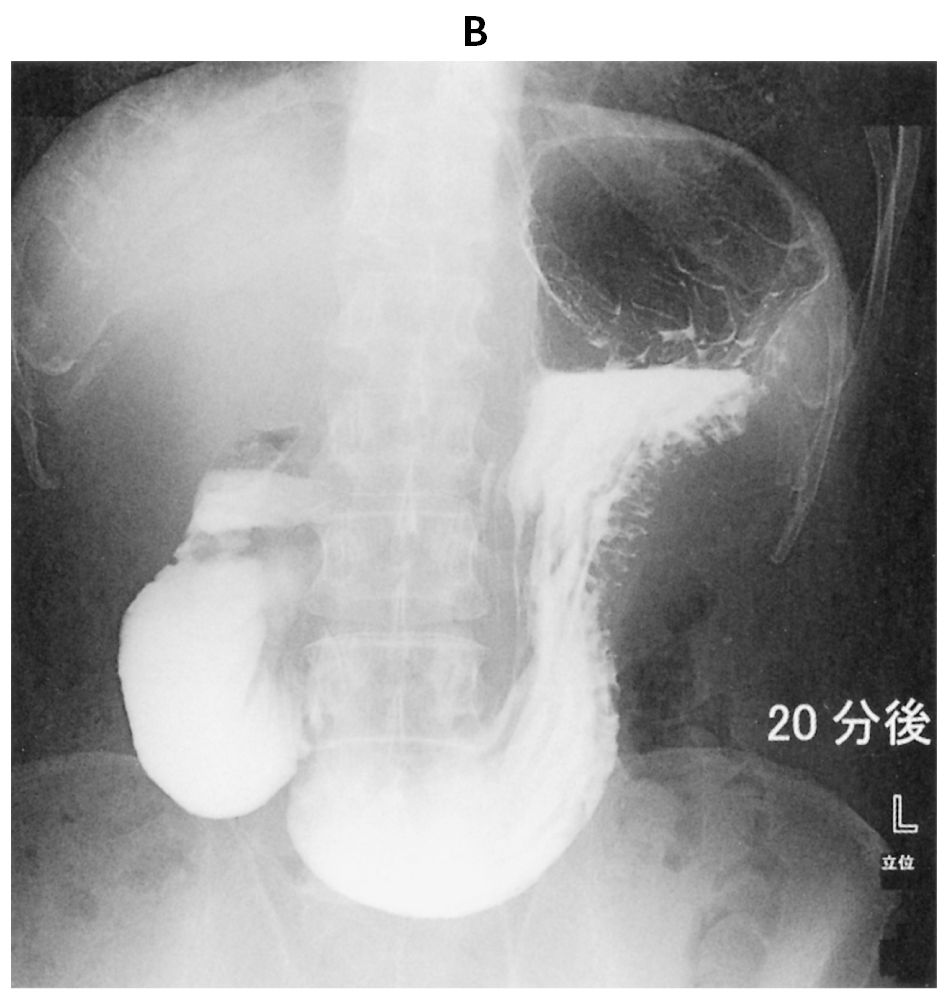

30歳の女性。嘔吐と体重減少を主訴に来院した。6か月前から仕事のストレスで食欲が落ち,体重が55kgから40kgまで減少した。その後,食後の悪心と嘔吐を繰り返すようになり,徐々に体重が減少するため受診した。上半身を前屈して食事をとると,食後の症状は軽減する。吐物に血液の混入は認めない。黒色便は認めない。意識は清明。身長160cm,体重35kg。体温36.5℃。脈拍72/分,整。血圧106/68mmHg。呼吸数20/分。SpO2 98%(room air)。眼瞼結膜は軽度貧血様であり,眼球結膜に異常は認めない。腹部は陥凹しているが,圧痛を認めない。血液所見:赤血球412万,Hb 10.2g/dL,Ht 38%,白血球5,600(好中球62%,好酸球3%,単球5%,リンパ球30%),血小板27万。血液生化学所見:総蛋白6.9g/dL,アルブミン3.3g/dL,総ビリルビン1.0mg/dL,直接ビリルビン0.4mg/dL,AST 17U/L,ALT 20U/L,尿素窒素28mg/dL,クレアチニン0.5mg/dL,CEA 2.5 ng/mL(基準5以下),CA19-9 17U/mL(基準37以下)。CRP 0.1mg/dL。水溶性造影剤による上部消化管造影像(A)(B)を下に示す。BAの20分後の像である。造影剤が十二指腸に停滞し,空腸への流出がみられなかった。